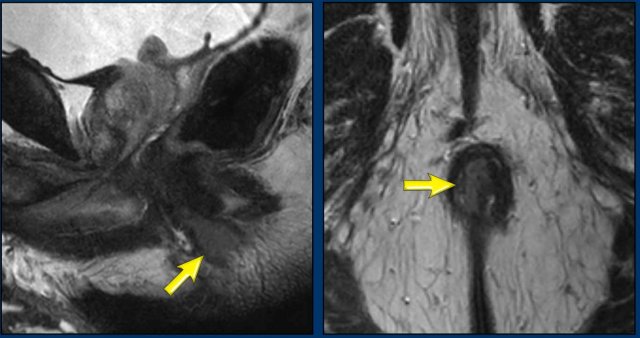

1. The internal sphincter (1) typically has an intermediate to low signal intensity on T2W MRI.

2. The fatty intersphincteric plane (2) has a high signal .

3. The striated muscle layers of the external sphincter (3), puborectalis (P) and levator ani (LA) have a low signal intensity.

When describing involvement of the internal and external anal sphincter, it is useful to describe both the cranioucaudal extent (e.g. upper half,  lower half or full length of the anal canal) as well as the level of circumferential involvement (e.g. from … till … o’clock).

Image

A tumor  involves the distal 2/3 of the anal canal.

It invades the internal sphincter, intersphincteric space and external sphincter from ± 12 till 3 o’clock.

There is no involvement of the pelvic floor, rectum or anal margin.

Another example showing a tumor that involves the proximal ½ of the anal canal.

It invades the internal sphincter, intershincteric space and  external sphincter from 7-10 o’clock.

The tumor invades the puborectalis and levator ani on the right (arrow) and extends just above the level of the anorectal junction (dotted line) into the distal rectum.